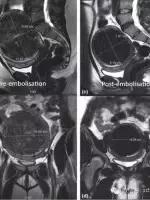

图a,b为介入栓塞术前的肌瘤大小,c,d为术后的肌瘤大小,肌瘤总体积从658ml降低到308ml。

另一病例,同样图a,b为术前子宫肌瘤大小,c,d为术后大小,体积从1300ml减小到129ml。